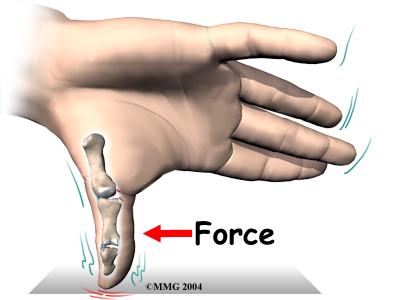

The joint that is affected is called the metacarpophalangeal joint, or MCP joint. Any hard force on the thumb that pulls the thumb away from the hand (called a valgus force) can cause damage to the ulnar collateral ligaments. When the thumb is straight, the collateral ligaments are tight and stabilize the joint against valgus force. If the force is too strong, the ligaments can tear. They may even tear completely. A complete tear is also called a rupture.

In Scottish gamekeepers, ligament damage in the MCP joint happened because the ligament stretched out after the gamekeepers repeated the same action over and over. Today, most cases of ligament damage in the MCP joint are caused from sports injuries. Now doctors tend to refer to the condition as skier's thumb, since it happens so often in downhill ski accidents.

Any extreme force that pulls the thumb away from the palm of the hand can damage the ligaments. The most common way for this to happen is to fall on your hand with your thumb stretched out. When a skier falls down while holding a ski pole, the thumb may get bent out and back, leading to an injury in the ulnar collateral ligament of the thumb.